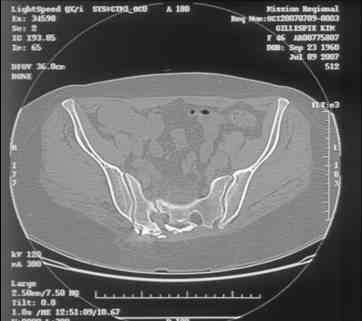

[Ortho] Sacral Non-Union

----------- следущая часть -----------

Вложение не в текстовом формате было извлечено…

Имя     : slide0001_image002.jpg